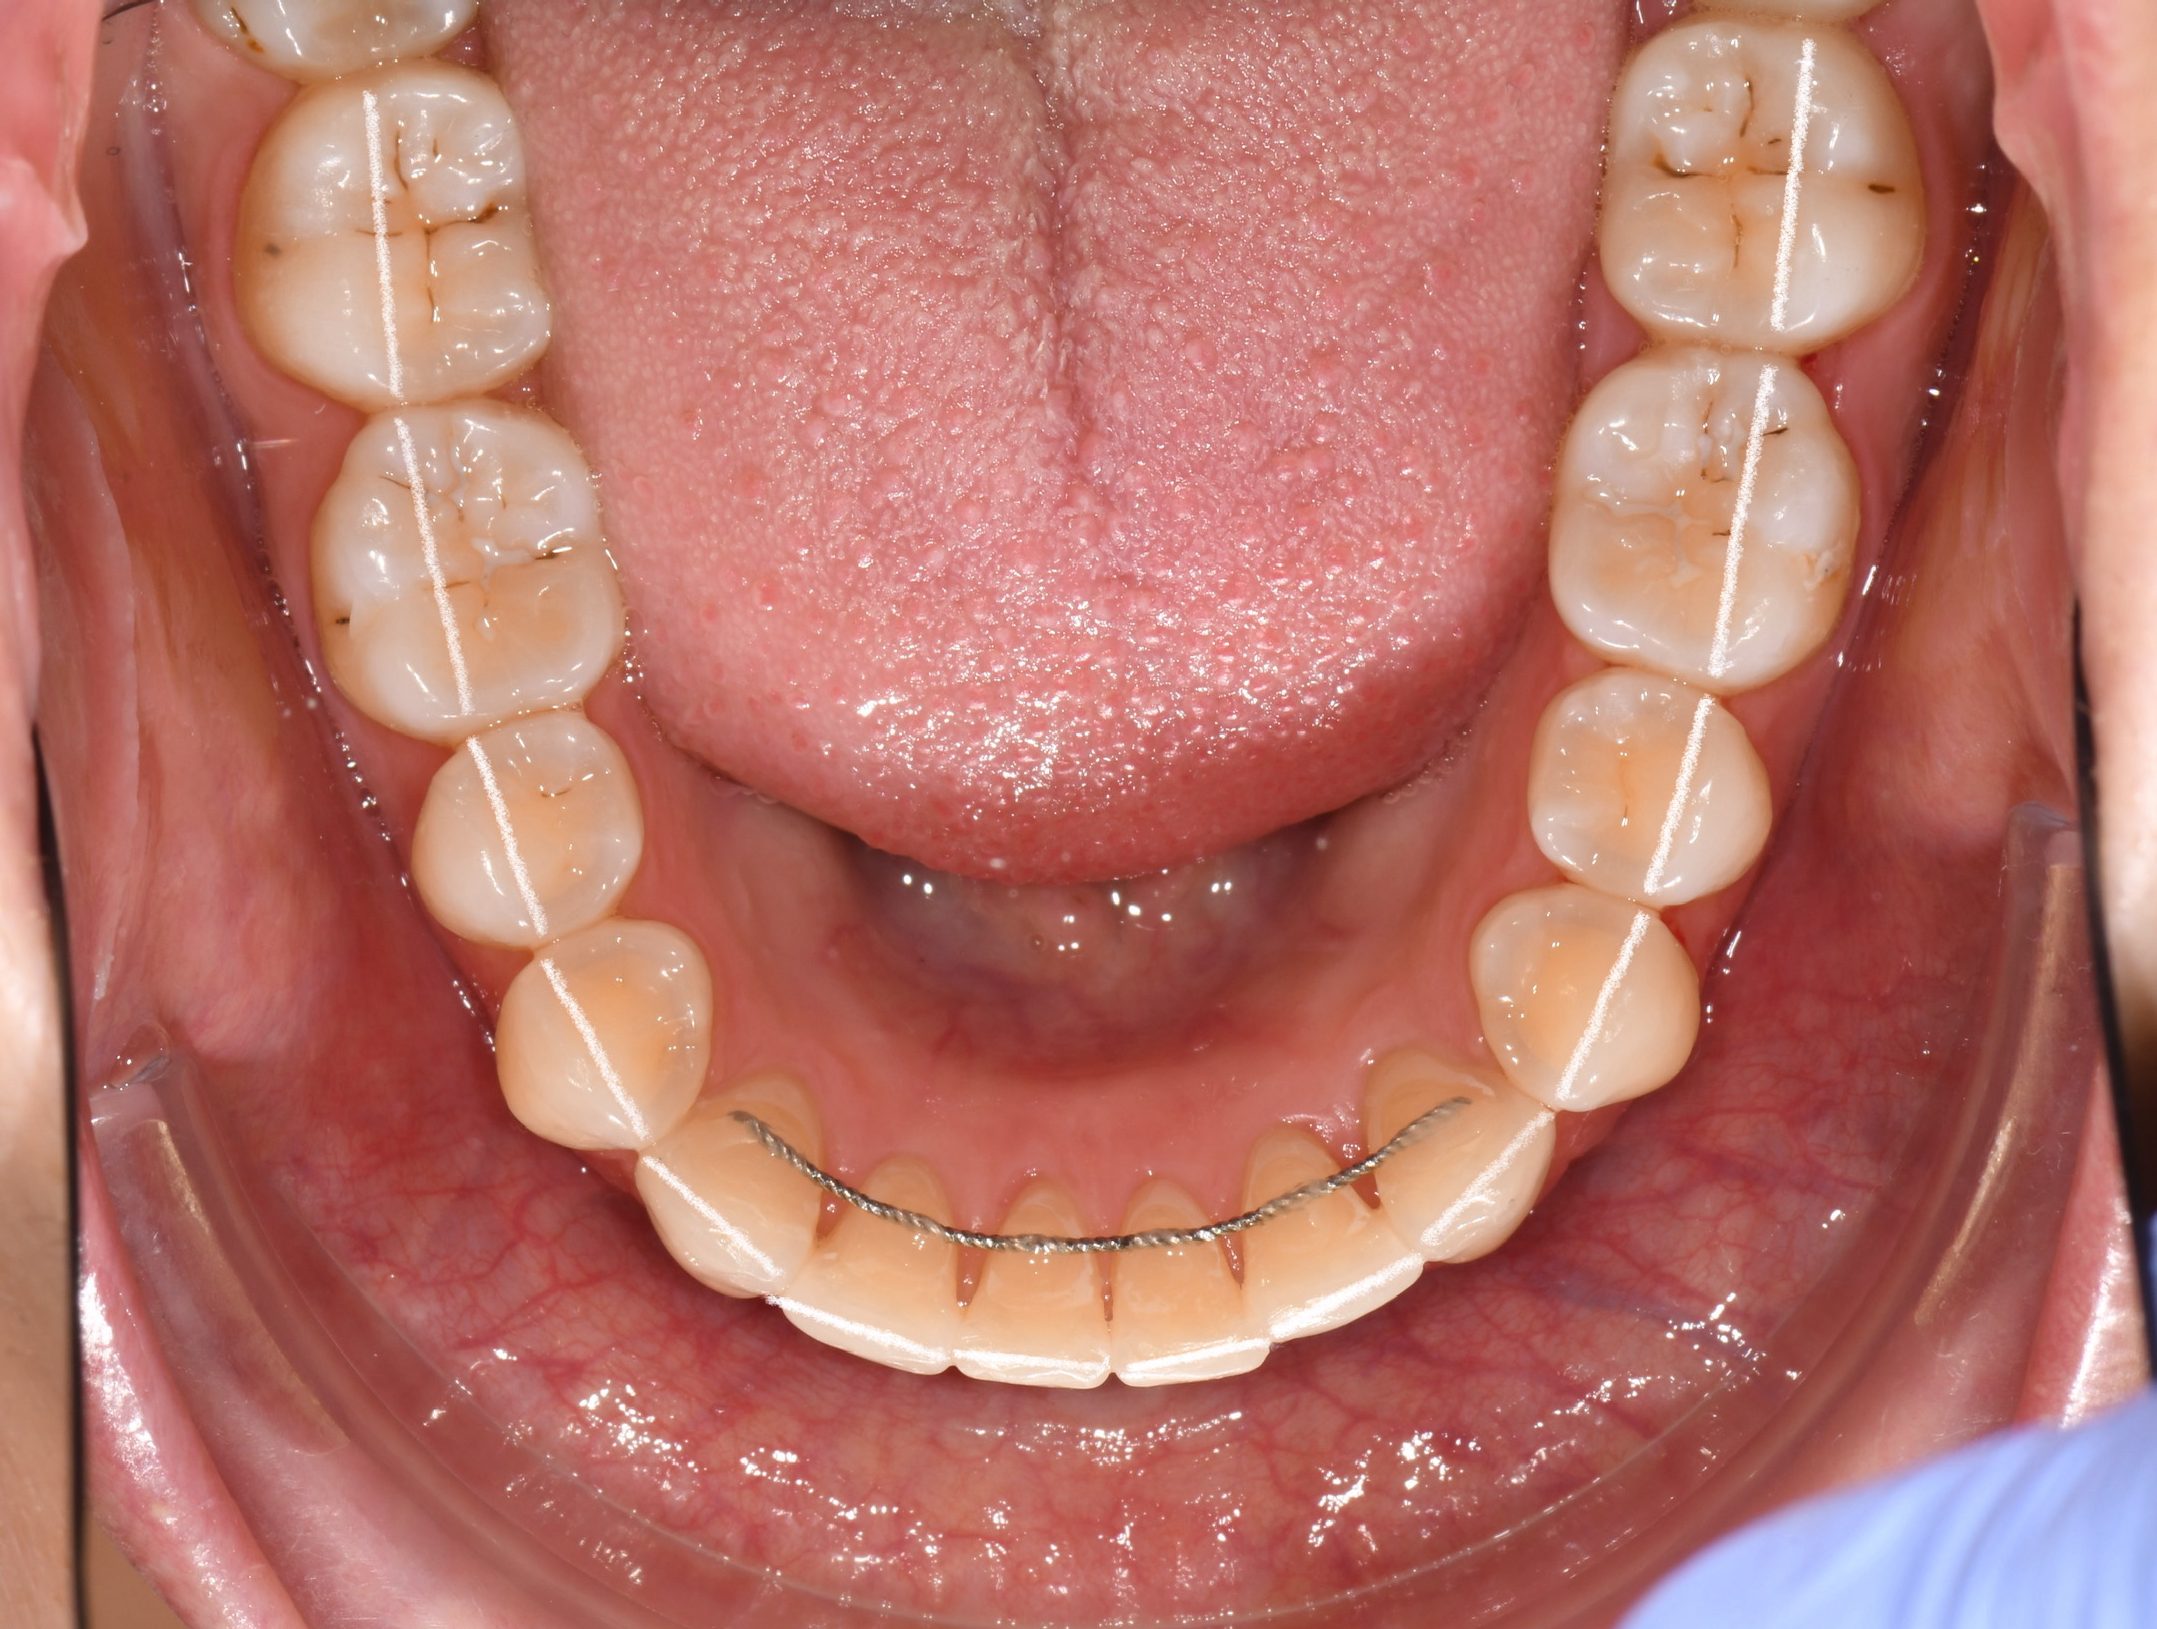

Az elmúlt évekből rengeteg szakmai referenciát tudnánk bemutatni, amelyek különböző fogszabályozási problémákat oldottak meg. Válogatva a több száz esetből, ezen az oldalon olyan képeket, információkat igyekeztünk bemutatni, amelyeknek a segítségével a jövőbeni pácienseinknek azt tudjuk üzenni: A Te fogsorod is lehet gyönyörű!

(Képeket a Pácienseink külön írásos beleegyezésével mutatjuk be!)